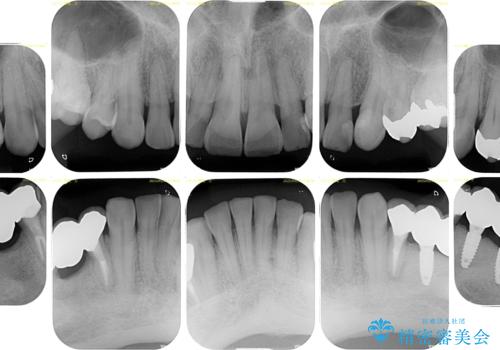

奥歯の欠損と前歯のデコボコを治したい インプラントと矯正治療の総合歯科治療

奥歯に欠損が多く、矯正治療はやや難航することが予想されますが、患者様の希望もあり、上顎左右小臼歯を1本ずつ抜歯し、ワイヤー装置にて矯正治療を行うこととしました。

矯正歯科治療を行うに当たり、痛みや違和感を感じている歯の根管治療を行い、矯正治療中にインプラント埋入し、補綴治療と矯正治療を同時に終了できるように進めて行くこととしました。

銀歯やむし歯治療されている歯を抜歯する治療計画としたため、やや時間はかかりましたが、治療後の仕上がりには大変満足していただけました。